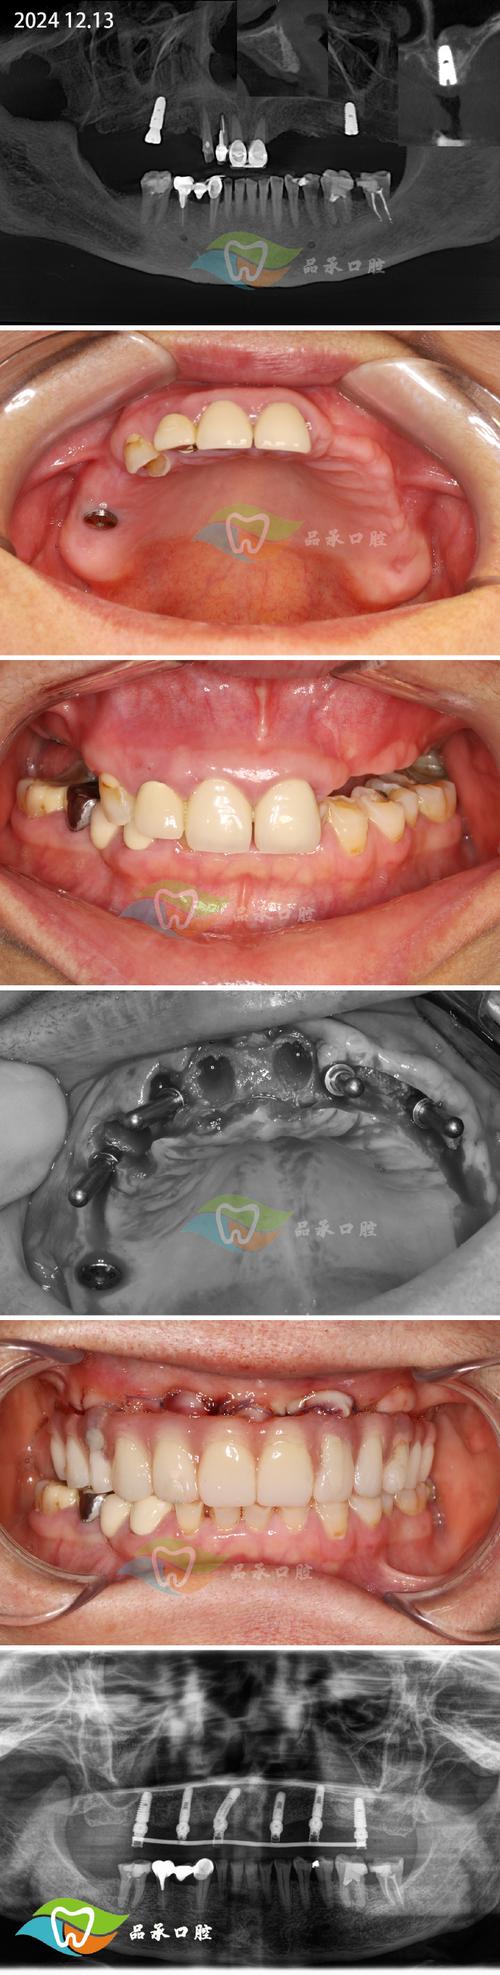

骨移植植牙手术需严格遵循“精准评估、无菌操作、生物相容”原则,通常分为术前准备、植骨手术、种植体植入及最终修复四个阶段,其中植骨手术是核心环节,具体流程如下:

通过CBCT(锥形束CT)三维重建测量牙槽骨的厚度、高度、密度及重要解剖结构(如下牙槽神经管、上颌窦底)的位置,结合口内检查和全身病史(如糖尿病、骨质疏松、吸烟史等),制定个性化手术方案,对于骨量严重不足者,可能需结合模型外科或3D打印导板辅助定位。

种植体植入与修复

植骨术后需等待4-6个月(自体骨可缩短至3-4个月),待移植骨与宿主骨完全整合(CBCT显示骨密度接近宿主骨),再行二期手术暴露种植区,植入种植体,术后3-6个月,待种植体与骨组织形成骨结合(osseointegration),最终完成牙冠修复,实现功能恢复。